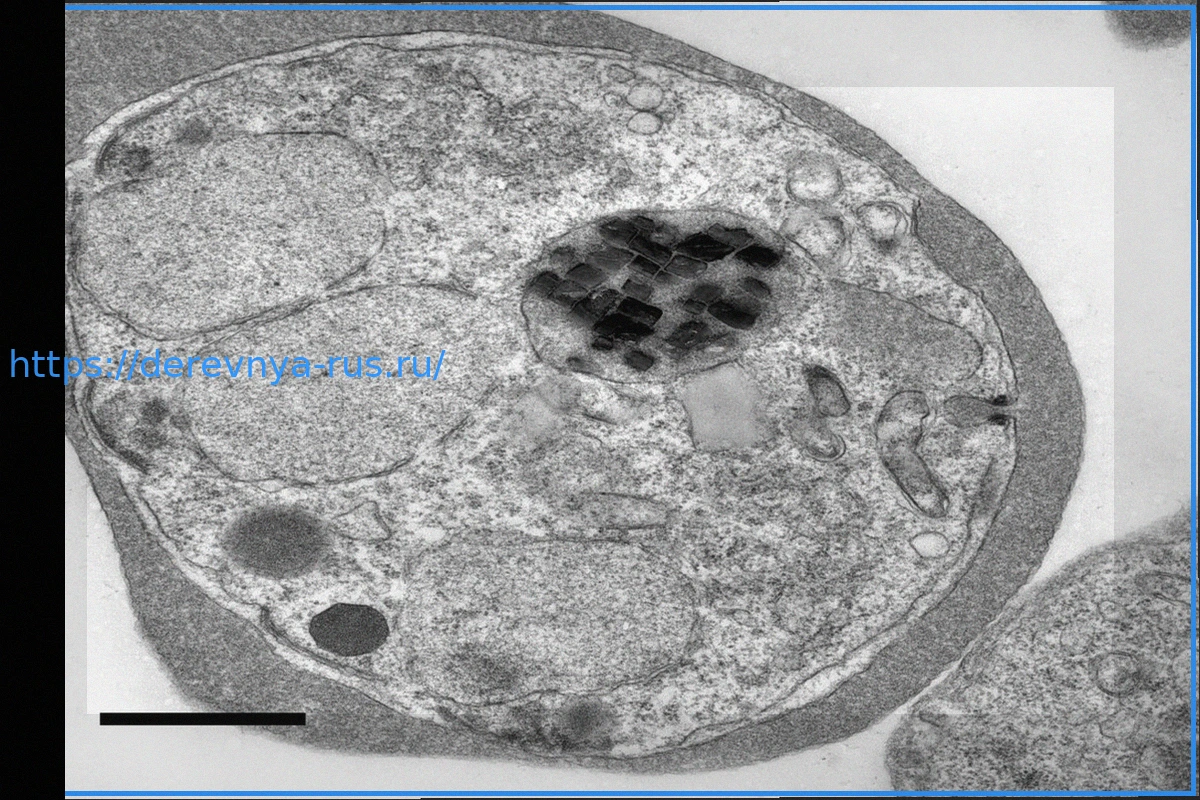

Малярийные паразиты содержат крошечные вращающиеся кристаллы, которые годами озадачивали ученых. Новое исследование показывает, что они приводятся в движение реакцией, подобной ракетному двигателю, которая расщепляет перекись водорода, высвобождая энергию. Это движение может помочь паразиту выводить вредные химические вещества и более эффективно управлять железом. Открытие может привести к созданию новых лекарств и стимулировать инновации в микроскопической робототехнике.